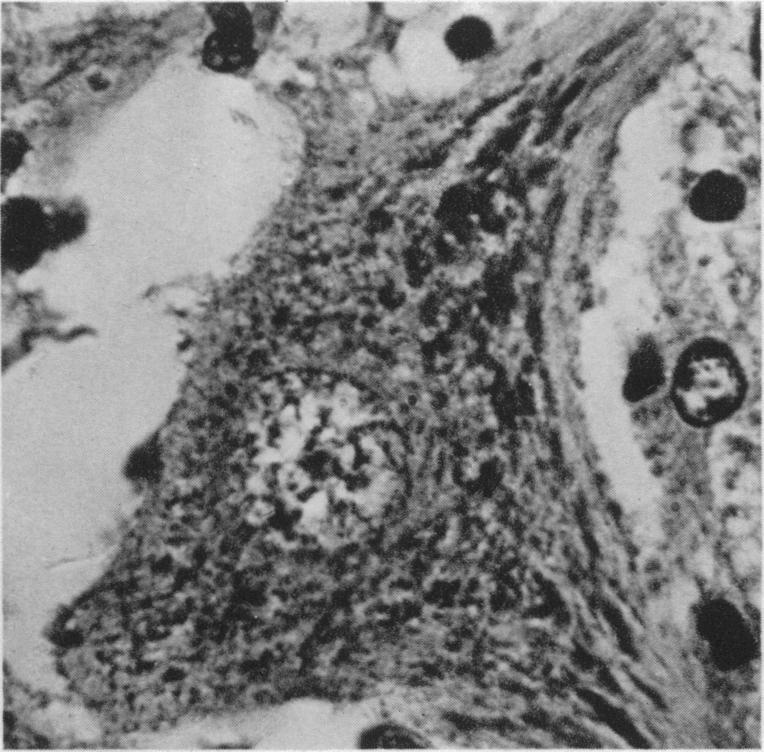

Rheumatoid arthritis in the young.

Br Med J. 1949 Jul 23;2(4620):197-201. doi: 10.1136/bmj.2.4620.197.